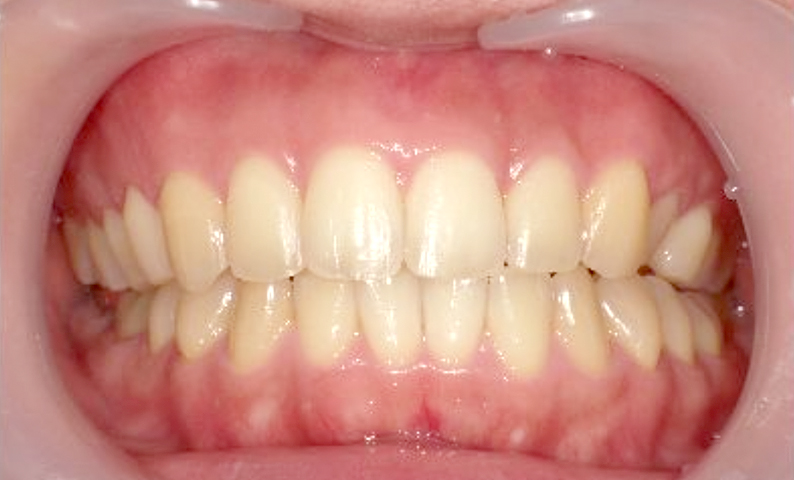

症例_024 上下顎の部分矯正

治療期間:13ヶ月金額:51万円+税女性前歯のガタガタ八重歯

| Before | After |